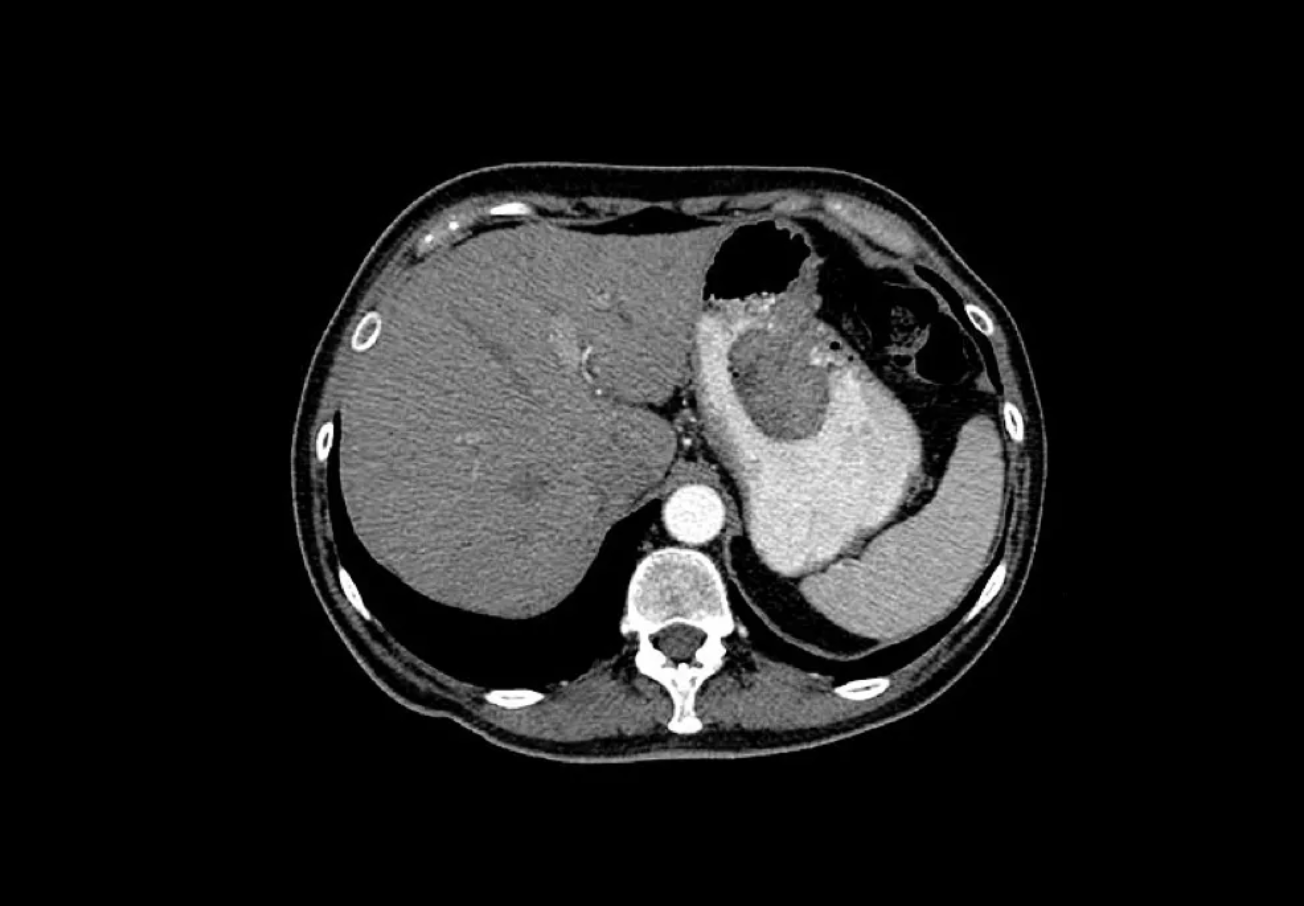

长期摄入过多盐分会破坏胃黏膜屏障,促进异常细胞增殖,增加胃癌风险。

▲胃癌CT扫描。图源:视觉中国

建议限制盐分摄入量,每天不超过5克。同时警惕“隐形盐”,拌饭酱、腐乳、酱油、鸡精、味精、饼干、薯片、话梅、方便面等都是含盐大户。